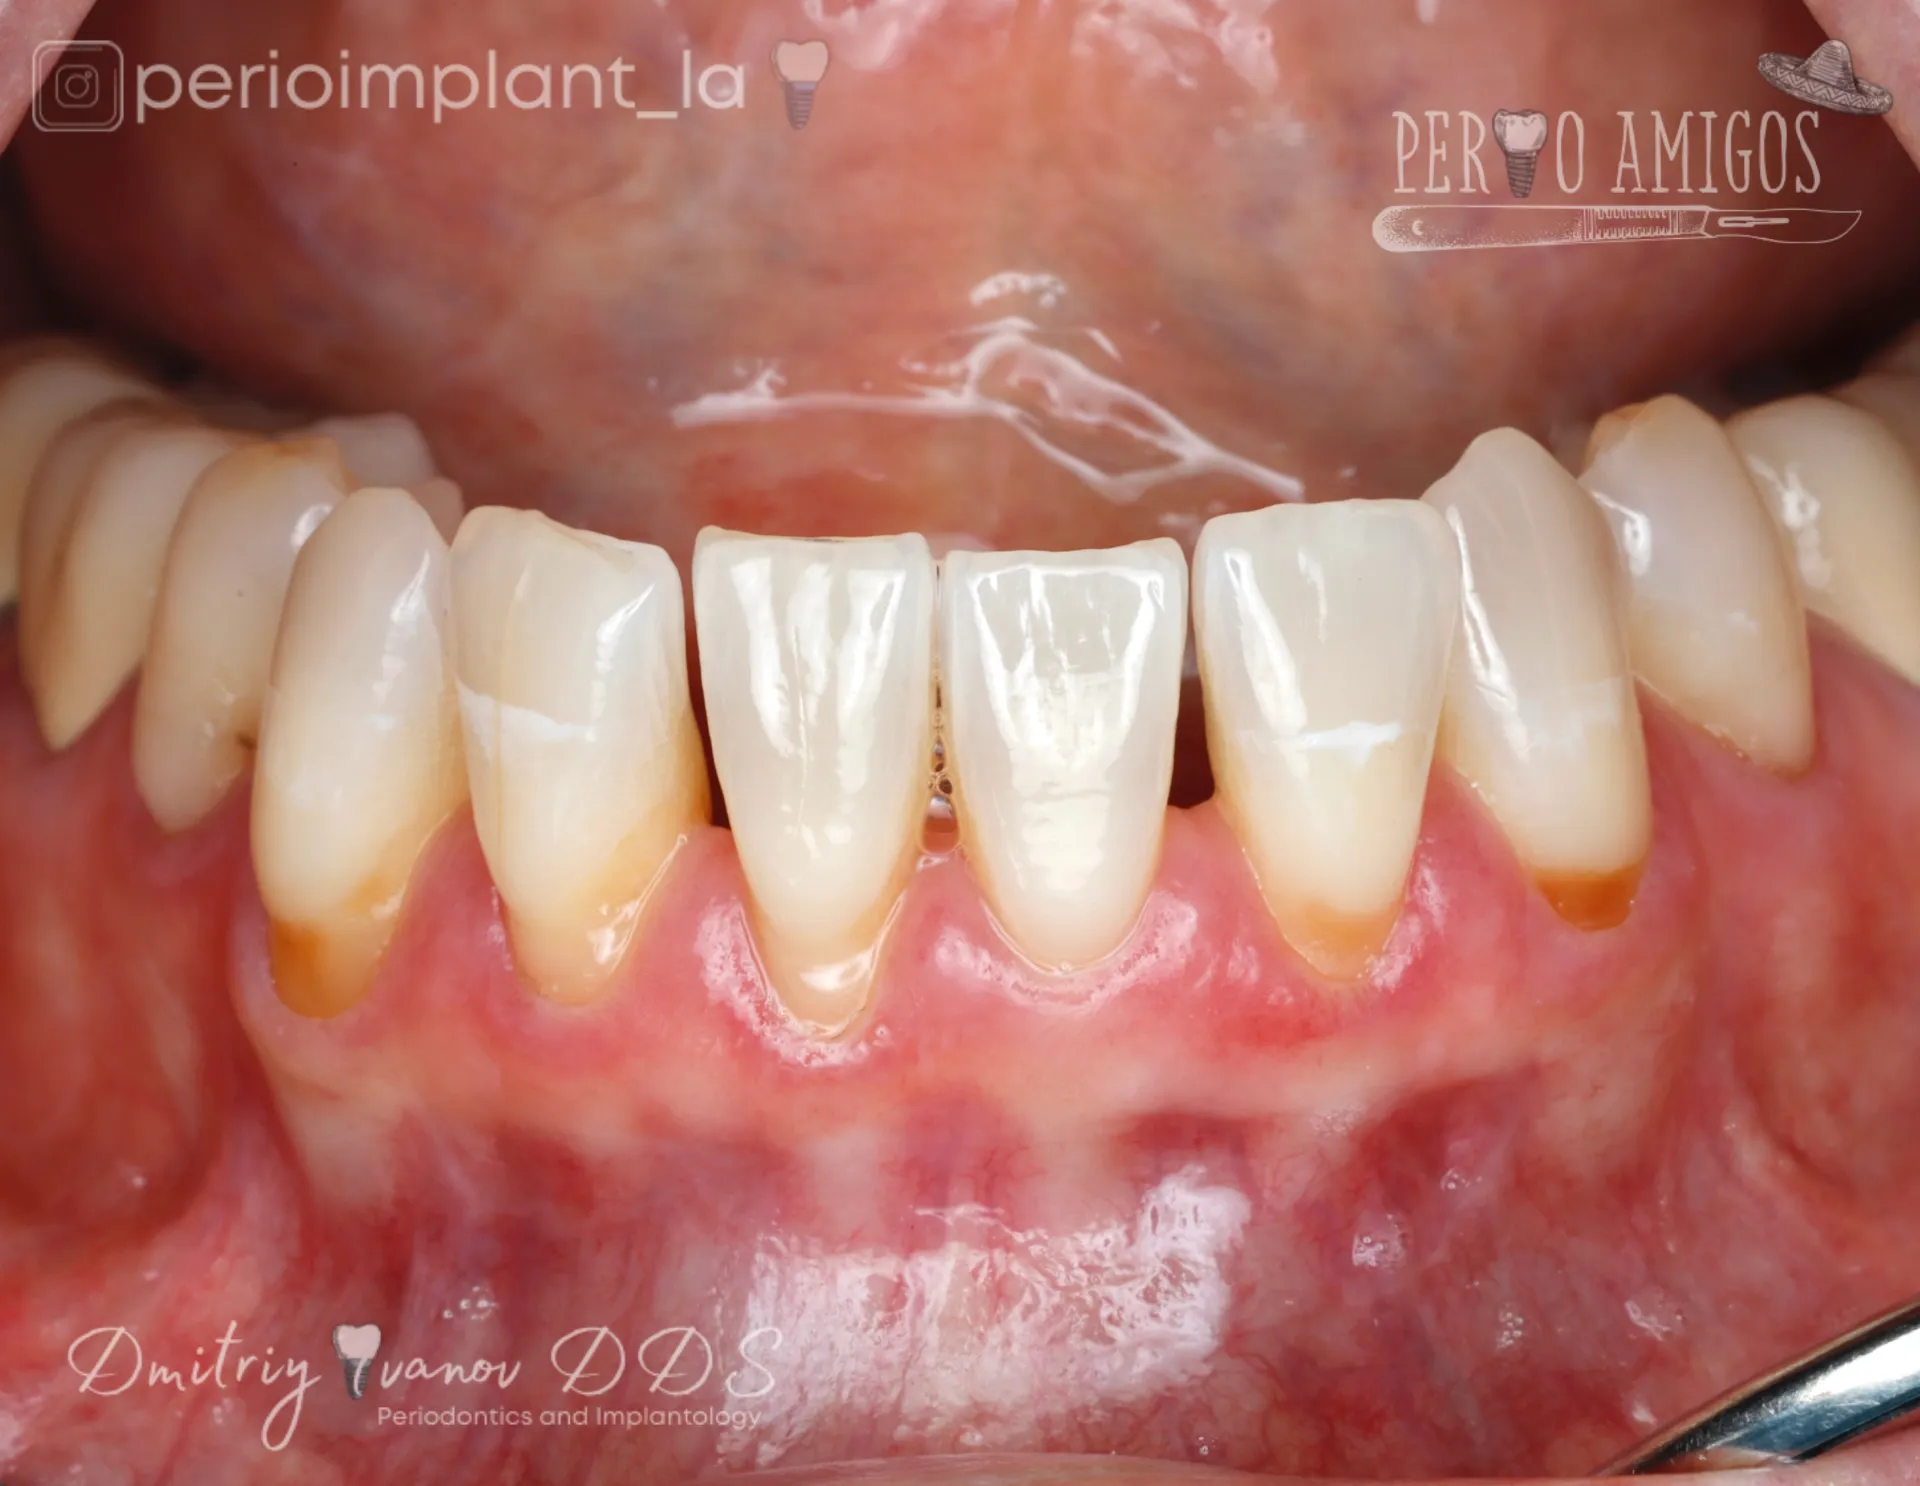

Gum Recession